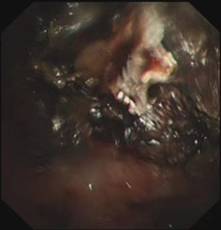

时间紧迫,每一秒都关乎生命,患者立即被送到内镜室,支气管镜检查的结果令人触目惊心:患者的总气管被痰痂、血痂、痰栓等物几乎完全堵死,仅残留一丝细小的通气通道,那是生命最后的脆弱纽带!

在紧张且充满紧迫感的抢救氛围中,呼吸介入团队成员默契配合,在支气管镜下使用异物钳夹取、超低温冷冻等方法清除异物。

随着每一次精准夹取和冷冻操作,顽固的异物被一点点从狭窄的气道内剥离出来,堆积在一旁的痰痂、血痂和痰栓逐渐增多,堆积起来的长度居然达到了惊人的18厘米。

当最后一块异物被取出,患者的气管终于露出了原来的“庐山真面目”: